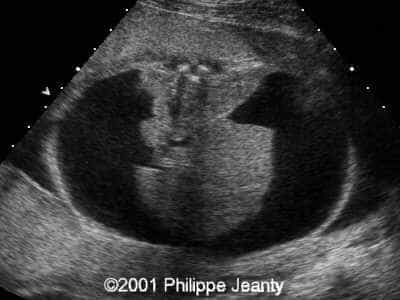

This 2nd trimester fetus has the following images (actually, these images remained unchanged for several weeks)

The findings are:

• very enlarged lungs on both sides

• inversion of the diaphragm that is convex towards the abdomen

• small compressed heart

• ascites but no generalized hydrops (no skin thickening for instance)

A much more common diagnosis for a bilateral echogenic lung associated with microcardia and ascites (Budd-Chiari phenomenon) is Larynx, atresia or as reported by several the CHAOS syndrome which stands for Congenital High Airway Obstruction Syndrome (which is typically laryngeal or tracheal atresia). This is the diagnosis that was indeed suspected in this fetus.

The patient was then referred to Dr. Ruben Quintero who managed to pass an endoscope in the fetal trachea. He created an opening, but unfortunately was not able to create a communication between the proximal and distal portion of the larynx, instead ending in the thoracic cavity. The fetus did well after the surgery (no premature delivery), although there was no improvement, and after a few more weeks of worsening of the lung condition the parents elected to terminate the pregnancy.